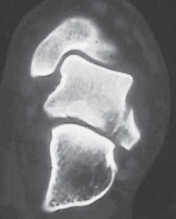

FIG 1 • Hawkins classification of talar fractures. A. Type I: disruption of anterolateral perfusion. B. Type II: medial perfusion intact. C. Type III: all D sources of blood flow injured. D. Type IV: dislocation of all articulations. 1. In the type III injury, the transverse fracture of the talar neck is associated with dislocation of the talar body. The incidence of osteonecrosis of the talar body is 50% to 100%. All major perfusion to the body of the talus is damaged ( FIG 1C). 2. A type IV injury of the talar neck has been documented; it is a type III fracture-dislocation with associated talonavicular dislocation.2 All extraosseous blood flow to the talus is considered disrupted. The value of the Hawkins classification is that it allows the orthopedic surgeon to predict what to expect with a specific talar neck injury. Open reduction and rigid internal fixation is the recommended treatment ( FIG 1D). 1. Talar body fractures are defined as fractures extending into or posterior to the lateral process. PATIENT HISTORY AND PHYSICAL FINDINGS 2. Fractures of the talus are commonly associated with vehicular trauma and falls. 1. The relationship of severe lower extremity trauma and airbags is well known. After airbag deployment, the torso and lower extremities are directed toward the floor panel of the car. 2. I believe that the incidence of high-energy hindfoot trauma will increase over time. Globally, transport related injuries remain the leading cause of disability from injury. By 2020, traffic injuries will increase from a current 9th position to 3rd disability-adjusted life years lost. 3. The history and the clinical status of the talar injury must be carefully recorded because the injury severity is likely to correlate with the long-term patient outcome. 1. On the initial examination the physician should note pain, motion, crepitus, deformity, soft tissue swelling, open fractures, and associated fractures of adjacent bones to the foot and ankle and should perform a complete neurovascular evaluation of the extremity. 4. Detailed documentation of the talus fracture pattern and local soft tissue injury is paramount. 1. Soft tissue local pressure phenomenon, commonly found anterolaterally in closed type III fractures of the talar neck, may precipitate full-thickness pressure necrosis of the skin if not decompressed early. 2. Severe swelling of the ankle is common in the acute fracture of the talus and may progress to fracture blister formation, precluding safe execution of operative incisions. 5. The physician should examine the skin for swelling, ecchy-mosis, fracture blisters, and deformity; these are signs of a closed fracture. 1. A closed injury with mild or moderate swelling (bony landmarks palpable) indicates talar neck type I and II fractures and process fractures. 2. A closed injury with severe swelling indicates talar neck type III and IV fractures and body fractures. 6. Open fractures will be apparent by the transverse, medial, or supramalleolar traumatic laceration of the ankle. Lateral, posterior, and plantar wounds are uncommon. 7. The physician should perform vascular, neurosensory, and myotendinous examinations of the foot and ankle. IMAGING AND OTHER DIAGNOSTIC STUDIES 8. Three plain radiographic views are necessary to radiographi-cally evaluate talus fractures: anteroposterior (AP), mortise (15-degree internal rotation view), and lateral images of the ankle. 1. The AP and mortise views of the ankle demonstrate alignment of the talar body in the ankle mortise. The lateral view depicts the sagittal outline of the talus. 9. The Canale view is used to assess varus or valgus malalignment of the talar neck, particularly with Hawkins type I and II injuries. The knee must be flexed and the foot in equinus and everted, with the x-ray tube directed 15 degrees caudad ( FIG 2A).

--- A B C ### FIG 2 • Radiology of talar fractures. A. Canale view showing medial and lateral talar neck provisionally reduced. B. Lateral process fracture less obvious on plain film. C. Lateral process fracture as shown on CT scan. 1. Because of the high-energy nature of fractures of the talus, AP and oblique views of the foot should be a standard addition to the three-view plain film ankle protocol so as not to miss associated midfoot and forefoot injuries ( FIG 2B). 2. Computed tomography (CT) provides important additional information to the three-view plain film series of the ankle. Thirty-degree coronal and paraxial CT imaging is important to confirm Hawkins type I fractures of the talar neck and plan treatment of talar body fractures with extension posterior to the lateral process. Reconstructions of both sagittal and coronal CT studies provide valuable information about incremental pathoanatomy of the entire talus, medial to lateral and anterior to posterior, respectively. In addition, confirmation of a process fracture that is not clearly viewed by plain film is easily diagnosed by CT ( FIG 2C). DIFFERENTIAL DIAGNOSIS 3. Process fracture of the talus 1. Lateral process fracture 2. Medial process fracture 4. Head of talus fracture 5. Neck of talus fracture 6. Body of talus fracture 7. Neck and body of talus fracture 8. Fracture-dislocation of talus 1. Involving body 2. Involving neck and body 9. Extruded talus (Any of these injuries to the talus may be open fractures, affecting management.) NONOPERATIVE MANAGEMENT 10. Fractures of the talus include a spectrum of injury patterns ranging from isolated regions of the talus (eg, lateral process) to severely comminuted talus fractures involving all parts of bone, making nonoperative management inappropriate. 1. High-energy injury mechanisms that cause talus fractures precipitate fracture displacement and joint surface incongruity. 2. Medial and lateral process fractures, minimally displaced (less than 2 mm) and involving less than 1 cm of bone, are commonly managed nonoperatively. 1. These injuries are treated acutely in well-padded, compressive dressings with posterior splints and non-weight bearing. Swelling and immediate pain in the ankle improve significantly by 7 to 10 days. The patient is subsequently converted to a short-leg non-weight-bearing cast for 6 weeks, followed by progressive range of ankle and subtalar motion and return to weight bearing in a removable fracture-boot. 2. If the process fracture is severely comminuted, precluding surgical reconstruction, the same initial and definitive nonoperative management is employed. 3. Isolated fractures of the head of the talus without dislocation and without displacement are largely stable fractures. These injuries require plain radiographic evaluation of both the ipsilateral foot and ankle to confirm the isolated nature of the injury. I recommend CT scanning (axial and transverse views of foot and ankle) of this injury to rule out associated midfoot pathology. 1. Acutely, an isolated, nondisplaced talar head fracture is splinted for 7 to 10 days with subsequent short-leg casting in neutral plantarflexion with non-weight bearing for 4 weeks. Intermittent daily ankle and subtalar motion with Achilles tendon stretching should follow with application of a removable fracture boot. The patient remains non-weight bearing until 6 to 8 weeks after injury. Next, progressive weight bearing, range of motion, stretching, and strengthening of the entire lower extremity are recommended. 4. The Hawkins type I fracture of the neck of the talus is a nondisplaced talar neck fracture. The talus remains anatomi-cally positioned in the ankle and subtalar joint with minimal potential for disruption of perfusion to the bone. 1. A subgroup of these injuries may present with displacement of the talar neck on initial injury plain radiographs. After closed manipulation of the fracture in plantarflexion, the talar neck fracture may reduce. A true Hawkins type I talar neck fracture will not displace even with gentle dorsiflexion. The type I fracture strongly warrants a CT scan, with sagittal reconstruction, to confirm anatomic alignment of the talar neck. 5. If there is displacement of the neck fracture, the injury must be reclassified as a type II, which requires surgical treatment to obtain, and maintain, the reduction. 1. Truly nondisplaced fractures of neck of the talus can be treated nonoperatively in a short-leg non-weight-bearing cast for 6 to 8 weeks. Close follow-up is recommended to watch for any displacement of the neck fracture. At 6 to 8 weeks after the injury, progressive weight bearing, range of motion, stretching, and strengthening are initiated. 10. Injury forces precipitating fractures of the dome of the talus are universally severe, causing articular displacement, and are an indication for surgery. Open fractures of the talus, even with no displacement, are best managed with rigid surgical stabilization to allow for wound care and early motion. SURGICAL MANAGEMENT 11. The timing of operative management of talus fractures has been an area of controversy, specifically whether the displaced talus fracture is an orthopedic emergency. 1. One recent study indicates that orthopedic trauma surgeons do not believe a displaced fracture of the neck of the talus is an orthopedic emergency. 2. However, it is important to differentiate the potential of vascular injury to the talar body from soft tissue and neurovascular compromise of the foot because of injury to the talus. In particular, fracture-dislocation of the body of the talus is associated with compromised blood flow to the bone, the threat of pressure phenomenon to the skin, and possible tibial nerve dysfunction. 3. The acute severity of soft tissue swelling or the impact of an open hindfoot wound may preclude safe, immediate reconstruction of the talus fracture after reduction of the dislocation. 12. Foot and ankle external fixation is a suitable treatment option, with staged definitive fixation applied accordingly. 1. Any open talus fracture must be treated as an orthopedic emergency. 2. Preoperative antibiotics may be selected on the basis of wound contamination. These include a cephalosporin and possibly gentamicin. Penicillin is added if gross or farm contamination is present. All patients should receive a tetanus toxoid booster. 3. The patient is taken to the operating room and after soft tissue débridement the wound receives at least 3 to 9 L of normal saline using pulsed lavage. 4. At this time, in addition to partial or complete fixation of the talus fracture, provisional foot and ankle external fixation may be used to provide soft tissue and osseous stabilization before delayed closure. 13. Regarding general guidelines for fractures of the body, neck, and head of talus fractures, surgical management is indicated with fracture displacement, malalignment, subluxation, dislocation, or instability. 1. Recent studies indicate that displacement or malalignment will have a negative impact on foot function. Two millimeters of fracture displacement has been shown to affect subtalar joint mechanics. 2. There is less agreement regarding surgical indications for process fractures of the talus. Acute, displaced fractures with large fragments showing extension into the subtalar joint by CT imaging are best treated with open reduction and internal fixation. 14. A displaced fracture of the neck of the talus is one of the most common indications for surgery on the talus. The fracture is known to start, in the coronal plane, along the medial neck and extend laterally until completion. 1. There are two common types of neck fractures: an extra-articular pattern and an intra-articular type that extends into the subtalar joint. 1. The displaced extra-articular vertical neck fracture is routinely amenable to closed reduction by applying dorsal-to-plantar pressure on the head of the talus associated with longitudinal traction and plantarflexion of the forefoot. Immediate reduction of this fracture diminishes concerns for soft tissue, neurovascular, and osseous compromise. 2. The intra-articular pattern is less likely to cooperate with closed manipulation owing to the obliquity of the fracture as it extends posterior into the subtalar joint. This fracture pattern is more deserving of immediate or early surgery. 15. For patients with severe open fractures of the talus, or closed injuries in which soft tissue compromise precludes immediate open management, temporizing external fixation may be effective. 1. The goals of temporary external fixation are to maintain the length of the talus for reconstruction, facilitate soft tissue management, and restore general alignment. External fixation is rarely definitive management for talus fractures. 2. Displaced, open or closed, fractures benefit most from rigid internal fixation for bone healing and early motion. However, a recent report evaluating results of the extruded talus identified definitive external fixation as an option to manage the purely dislocated talus. This is an excellent treatment option to stabilize the ankle and subtalar and talonavicular articulations of the talus. Preoperative Planning 16. Operative planning for talus fractures requires evaluation of imaging studies to clearly understand the relationships of all major fracture fragments. 1. A preoperative CT scan of the fracture is standard when confronted with a comminuted talar neck or body fracture. The surgeon must become familiar with the morphology of the bone and its many contours to facilitate reconstruction. 17. Intraoperative visibility and access to talar fragments are routinely challenging, but these variables can be largely facilitated by correct patient positioning, surgical approaches, adequate operating room lighting (headlamp), attention to reduction techniques, and implants selected. All play a key role in preoperative planning. 18. The principles of open treatment are restoring articular con-gruity, maximizing the revascularization potential of the bone, and allowing early motion of the ankle and subtalar joints. 19. The use of a radiolucent table and a headlamp promotes optimal visualization. 20. A tray of fine-tipped, sharp and strong bone elevators, dental probes, Freer elevators, small bone clamps, mini/small lamina spreaders, and small distractors or external fixation equipment is routinely needed not only for talus fracture fixation but also all fine articular fracture reconstructions. 1. Small interfragmentary (3.5 mm) cortical screw fixation and mini-fragment (2.7 or 2.0 mm) screw/plate instrumentation is commonly needed for talus fracture fixation. 1. An extra-long mini-screw (2.7 or 2.0 mm) inventory is recommended, with screws up to 60 mm long. 2. The use of mini-implants is particularly helpful when reconstructing comminuted fractures. 1. Contemporary mini-fragment systems are predominantly stainless steel. 2. Some authors have suggested using titanium implants to allow use of magnetic resonance imaging to assess osteonecrosis. 3. Osteochondral fragments too small for mini-fragment fixation can be fixed with bioabsorbable pegs or headless articular screws. Positioning 3. Displaced fractures of the head, neck, body, and lateral process of the talus are best reconstructed with the patient in the supine position. 1. Supine positioning allows medial, anterolateral, and direct lateral incisions to be performed with ease ( FIG 3A,B). 2. Intraoperative fluoroscopy is conveniently performed with the patient in this universal position. 3. The patient should have an adequate bump placed preop-eratively under the ipsilateral gluteal region to avoid external rotation of the ankle. 4. Fractures of the posterior body of the talus are performed through posteromedial or posterolateral surgical approaches. These approaches are achieved most efficiently with the patient in the prone position ( FIG 3C). 5. The prone or lateral recumbent position is effective for occasional posterior-to-anterior fixation associated with minimal or no displacement of the fracture. 6. A radiolucent table without attachments at the foot allows for all required radiographic views. Approach